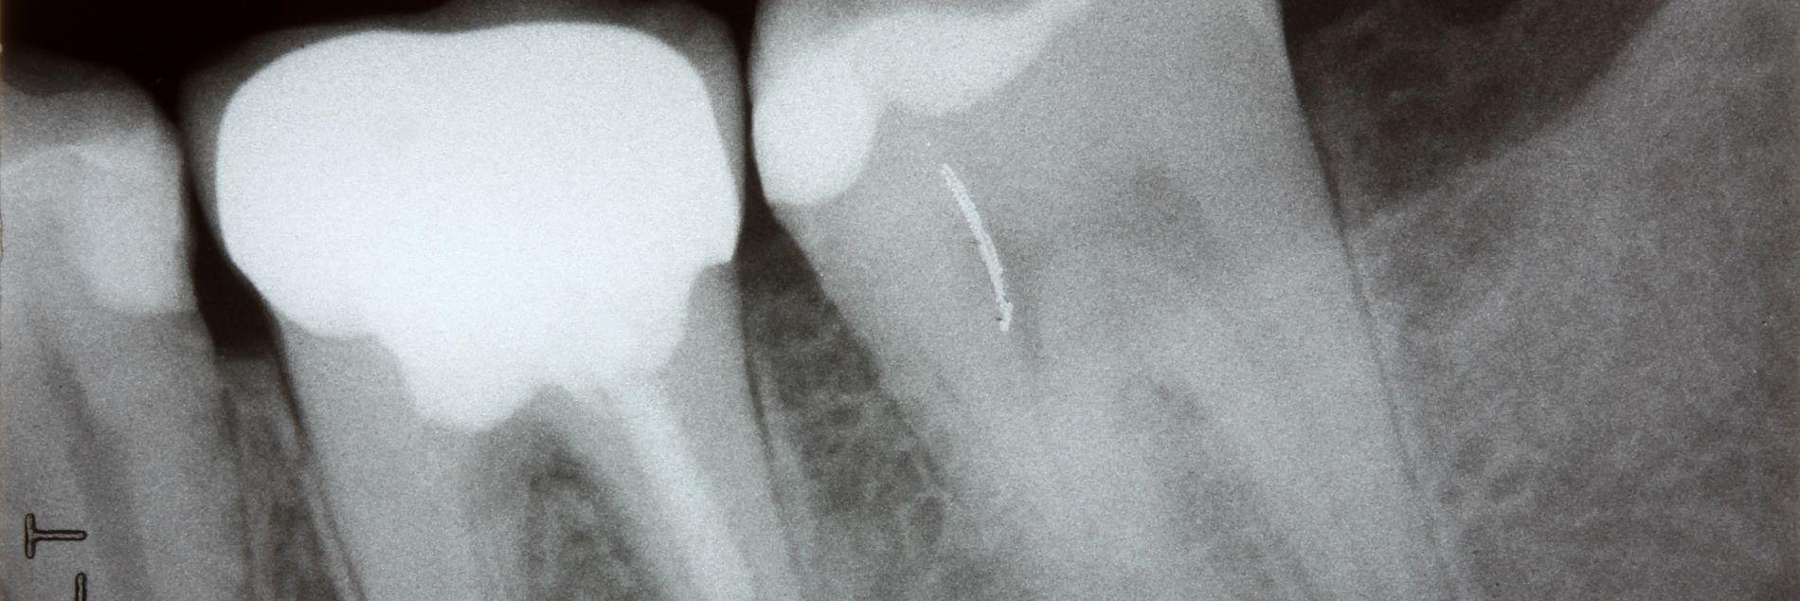

image of wisdom teeth in doreen vic

However, sometimes, your wisdom teeth may be impacted. This means they are coming in at an angle and can’t erupt properly, or there isn’t enough room for them to erupt. When this happens, your dentist may need to make an incision in your gums to access your wisdom teeth and remove them.